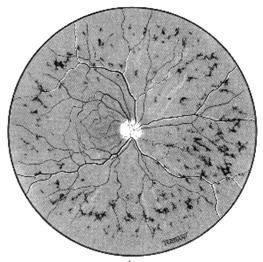

remanierile pigmentare apar mai ales la nivelul retinei periferice, sub forma de pete pigmentare stelate cu aspect osteoblastic, mai ales perivascular (Fig -17.7, vezi plansa).

Fig. 17.7 - Retinopatie pigmentara